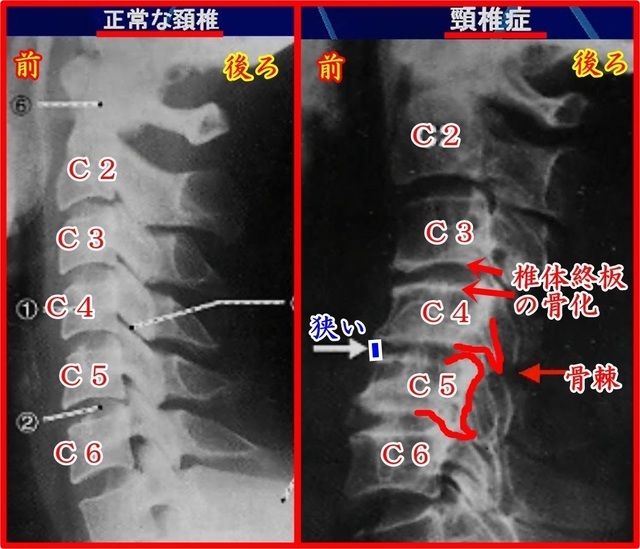

右の画像は正常な頸椎と頚椎症の比較画像です

向かって左側が正常な頸椎。右側が頚椎症になります。

●正常な頸椎と頚椎症の比較解説

正常な椎骨はなだらなか前弯であるのに対して頚椎症はC2~C4あたりが後弯しているのがわかると思います。

椎間板の幅を見ると頚椎症はC4-C5あたりが狭くなっています。

椎体終板(椎体と椎間板を繋ぐ組織)カルシュウムが付着して骨硬化が起こります。

頚椎症のレントゲンを見ると椎骨が白い枠状になっているのが骨硬化を示しています。

この椎体終板が骨硬化することで椎骨から椎間板に流れる栄養素が阻害され退行変性が進んでしまいます。

さらに骨棘がたくさんあるのが見えます。